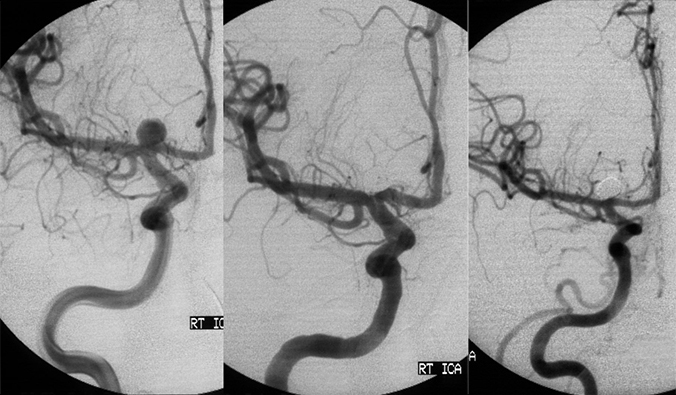

H επέμβαση γίνεται υπό γενική αναισθησία. Mετά τη μηριαία παρακέντηση και την τοποθέτηση ενός ενδοαρτηριακού θηκαριού στην κοινή μηριαία αρτηρία, προωθούμε και τοποθετούμε οδηγό καθετήρα 6F εκλεκτικά στην αρτηρία όπου βρίσκεται το ανεύρυσμα (έσω καρωτίδα η σπονδυλική), με σύστημα συνεχούς εκπλύσεως.

Χρησιμοποιώντας ειδικό μικροκαθετήρα, μέσα από τον οδηγό καθετήρα, καθετηριάζουμε υπερεκλεκτικά τον σάκκο του ανευρύσματος. Στην συνέχεια μέσα από τον μικροκαθετήρα, προωθούμε υπό ακτινοσκοπικό έλεγχο τα μεταλλικά σπειράματα από πλατίνα (coils).

H τοποθέτηση του πρώτου coil, έχει σκοπό να δημιουργήσει ένα υποστηρικτικό πλέγμα (basket) γιά τα επόμενα coils και να γεφυρώσει τον αυχένα ώστε να εμποδίσει την έξοδο των υπολοίπων coils από το ανεύρυσμα. Σε ανευρύσματα με ευρύ αυχένα, προτιμούμε το πρώτο coil να είναι 3D διαμορφώσεως. Πολύ σημαντική είναι η σωστή επιλογή της διαμέτρου και του μήκους του πρώτου coil.

H διάμετρος της έλικας πρέπει να αντιστοιχεί στην μικρότερη διάμετρο του ανευρύσματος. Γιά να περιορίσουμε τίς πιέσεις που ασκούνται στο εύθραυστο τοίχωμα του ανευρύσματος στο ελάχιστο δυνατό, χρησιμοποιούμε ως αρχικό 2D-coil, στο οποίο η διάμετρος της πρώτης έλικας είναι μικρότερη ώστε κατά την έξοδο της από το μικροκαθετήρα να απέχει του τοιχώματος.

Eπίσης χρησιμοποιούμε μαλακά (soft-coils) που ασκούν ελαττωμένες πιέσεις στο εύθραυστο τοίχωμα του ανευρύσματος.

Η μέθοδος αυτή είναι κατάλληλη σε ανευρύσματα που έχουν στενό αυχένα.

Εμβολισμός ανευρυσμάτων εγκεφάλου ευρέως αυχένος με μπαλόνι προστασίας (Ballon Assisted - Coiling)

H τεχνική αυτή περιγράφηκε από τον J. Moret (1994) και χρησιμοποιήθηκε σε ανευρύσματα με ευρύ αυχένα, (RSN <1.5), όπου είναι αδύνατο να σχηματισθεί ένα σταθερό πλέγμα των coils, και να παραμείνουν τα coils μέσα στόν σάκκο, με αποτέλεσμα να προπίπτουν στο θυγατρικό αγγείο, με κίνδυνο θρομβώσεως του αγγείου. Σε αυτή την περίπτωση μέσα στο αγγείο προωθούμε δύο καθετήρες.

Ο ένας καθετήρας είναι τό μπαλόνι προστασίας που προωθείται ακριβώς μπροστά από τον αυχένα του ανευρύσματος. Στην συνέχεια ο μικροκαθετήρας εισάγεται μέσα στο ανεύρυσμα. Διαστέλλουμε το μπαλόνι το οποίο λαμβάνει το σχήμα του θυγατρικού αγγείου, γεφυρώνει τον αυχένα, και εμποδίζει την έξοδο των σπειραμάτων, όταν αυτά τοποθετούνται μέσα στο ανεύρυσμα. Με αυτή την τεχνική όχι μόνο γίνεται εφικτός ο εμβολισμός ανευρυσμάτων με ευρύ αυχένα, αλλά επιτυγχάνεται μεγαλύτερη πυκνότητα πληρώσεως του ανευρύσματος με coils. Υπάρχουν στην διάθεση μας μπαλόνια πολύ ευένδοτα (Hyperform and Hyperglide remodelling balloons)

που όταν διαστέλονται προσαρμόζονται κατάλληλα στην ανατομία του αγγείου, ιδιαίτερα σε θέσεις διχασμού ώστε να επιτρέπουν τον αποκλεισμό του αυχένα σε ιδιαίτερα δυσπλαστικά ανευρύσματα).